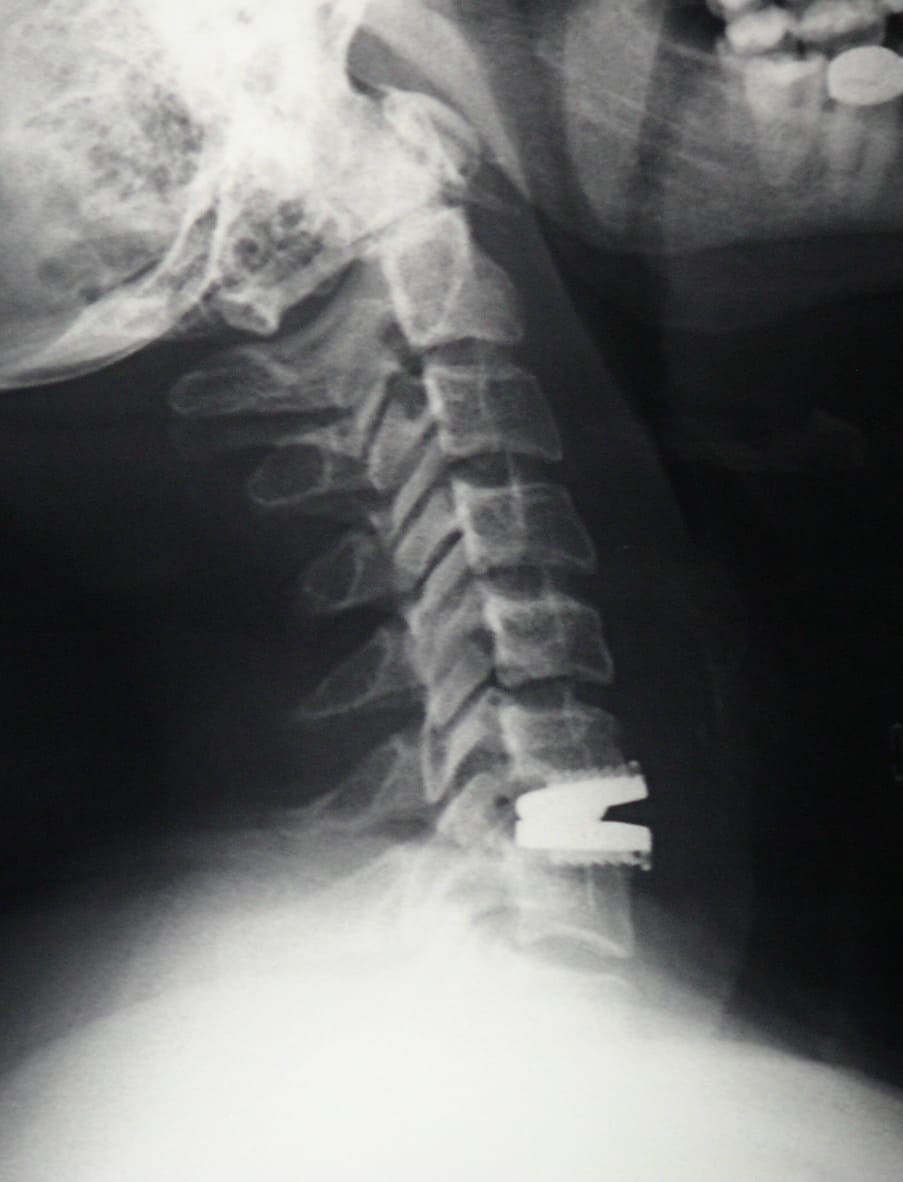

Puede requerirse una radiografía para descartar otras causas del dolor de espalda, como la osteoartritis. La tomografía computada o la resonancia magnética verifica la extensión y localización del daño al disco. En ocasiones se requiere una mielografía.

Cuando se trata de aliviar la presión sobre un nervio y el dolor de cuello, la cirugía usualmente incluye una extracción completa del disco o discectomía, seguido por el implante de un dispositivo espaciador o una prótesis total de disco. Esta cirugía se hace en la parte anterior del cuello (se le llama microdiscectomía y artrodesis o prótesis discal anterior). Afortunadamente, estos procedimientos muchas veces pueden realizarse usando técnicas de invasión mínima. La cirugía de invasión mínima no requiere incisiones grandes, sino que hace pequeños cortes y usa instrumentos y dispositivos minúsculos especializados durante la operación, como un microscopio y un endoscopio.